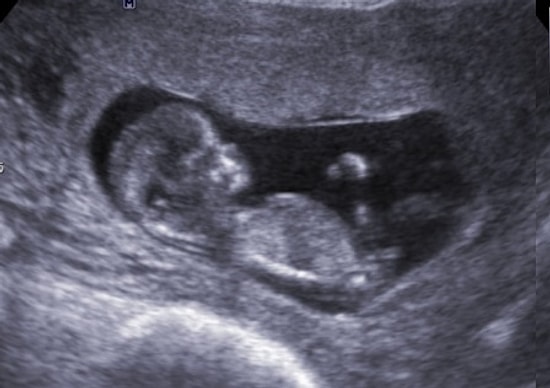

23 yaşındaki Hannah Taylor, doğum hakkında annesinden duyduğu 'korkunç' hikayelerle büyüdü ve şu an üç aylık olan oğlunu kucağına alabilmek için daha rahat bir doğum istedi. Tıbbi yardım almadan doğumunu gerçekleştirmeye karar verdikten sonra, açık havada bir küvette çocuğunu dünyaya getiren çiçeği burnunda annenin fotoğrafları ilham veriyor. The Sun kaynaklı hikayemize bir göz atın.